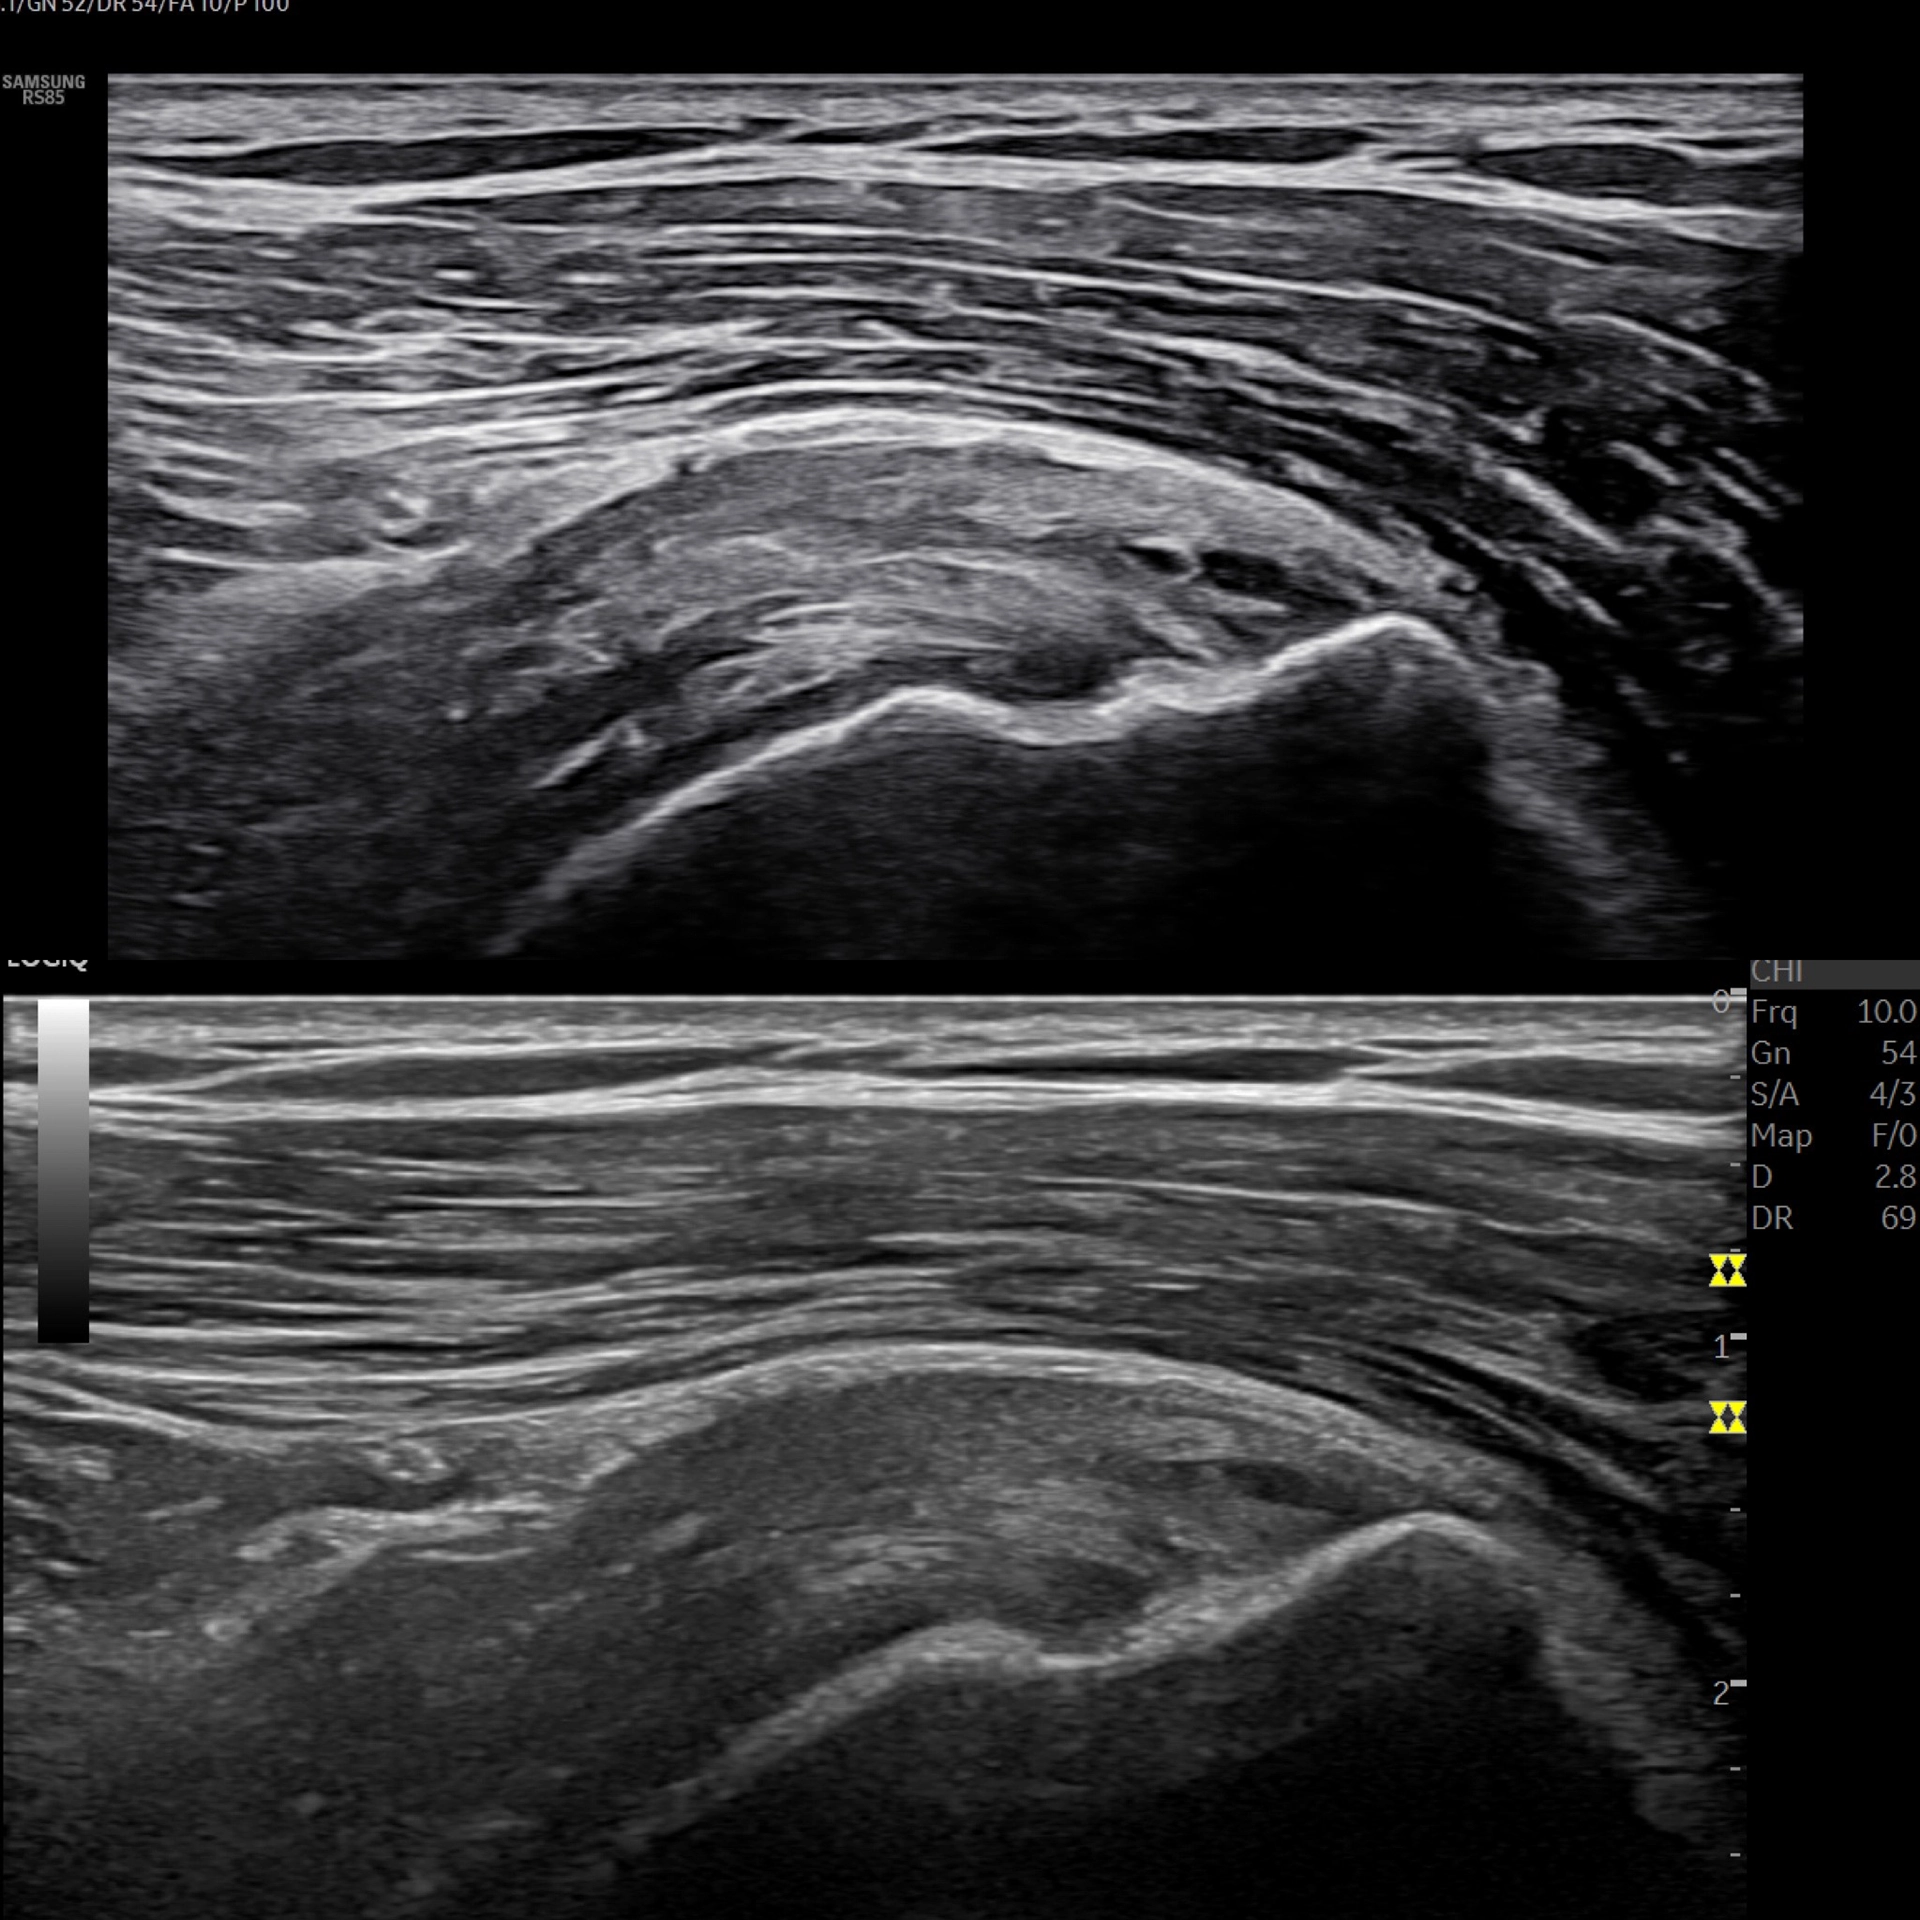

MSK ultrasound equipment

Ortomed and Skadekompassens OMI-specialist, Mikael Boije af Gennäs, at Shoulder Rehab Sweden ultrasound scanning course.

• Image contrast: High contrast with deep blacks and strong brightness; clear differentiation of layers & fibrous structures (slight graininess acceptable if contrast is excellent)

• Split screen: True side-by-side comparison of two images; both full images must be shown (scaled down), not cropped

• Depth for MSK: Reliable imaging down to 5–6 cm (appropriate lower frequency support for deeper structures)

• Software mode: Trapezoidal / Virtual Convex imaging on the linear probe (wider field of view for joints such as shoulder and hip)